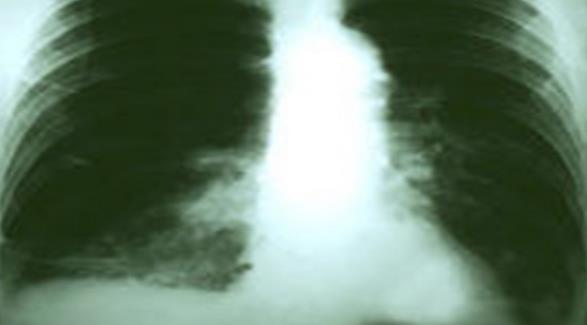

肺癌是常见的呼吸系统癌症,在美国患有肺癌的患者不计其数。手术是治疗肺癌的常见方法,一项前沿研究显示,老年肺癌患者进行外科手术治疗后,存活时间变长。

该项研究中,研究者分析了美国2002年到2012年之间,数以万计的65岁以上肺癌患者进行外科手术的治疗数据。分析得知,一期肺癌患者进行手术治疗后的存活期中位数为6.7年——较之基5年的准生存率高了两年。

分析结果还显示,在某些肺癌晚期的老年患者中,三期肺癌患者5年生存率提高至30%,四期肺癌患者5年生存率提高至27%。